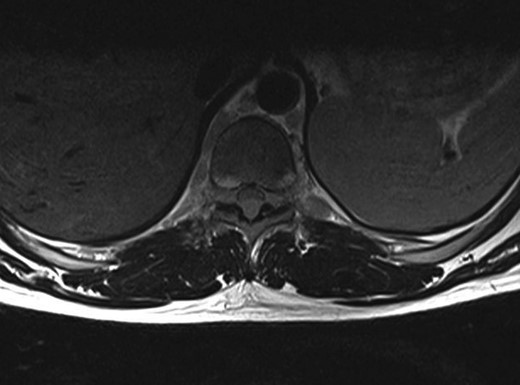

A 30-year-old male patient was admitted to our clinic with back pain. Pain was provoked by movements. The severity of pain was associated with the inability to perform the activities of daily living. The patient did not have any lymphoma-related B-type symptoms, including body weight loss, fever and sweat at night. He did not have a past and family history. There was no neurological deficit. Routine laboratory test results were normal. A magnetic resonance imaging (MRI) scan of the thoracic spine demonstrated an epidural tumor at the T9–11 level (Figs 1–3). The patient underwent spinal cord decompression via total laminectomy of T9–11 levels. Subtotal resection of the tumor was performed. Histological examination revealed the polymorphous cellular infiltration by histiocytes, large mononuclear cells and lacunar Reed–Sternberg cells with folded multi-lobed nuclei and small nucleoli (Fig. 4). Immunohistochemical staining was positive for CD15 and CD30 and negative for CD3, CD20, CD79a or CD45Ro. These features were most frequently observed in the mixed cellularity type of Hodgkin's lymphoma. Histological examination of the vertrebral body revealed no abnormality. The results of all other examinations (F-18 fluorodeoxyglucose positron emission tomography (F-18 FDG PET/CT), bone marrow biopsy and computed tomography (CT) of the chest, abdomen and pelvis) were negative for an occult disease. The patient was referred to the hematology department to undergo staged treatment. Six courses of chemotheraphy containing ABVD regimen (adriamycin, bleomycin, vinblastine and dacarbazine) were given to the patient. Postoperative MRI scan did not reveal any evidence of Hodgkin's disease (Fig. 5), F-18 FDG PET/CT, CT of the chest, abdomen and pelvis were obtained in 24 months and did not reveal any evidence of Hodgkin's disease.